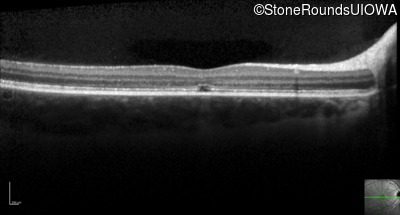

Optical Coherence Tomography - Right - 20/160 +2

Exemplar / OCT Stack

OCT Stack